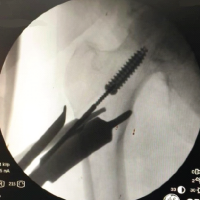

Finally, attention was made to the rotator cuff. There was an identified anterior leading edge tear to the subscapularis, shown in Fig. 2.

Figure 2: Arthroscopic visualization of the subscapularis with a Type I anterior leading edge tear, showing longitudinal splitting of the anterior edge with fraying of the tissue.

The repair began by using a biologic augmentation approach with decortication to allow for a bleeding bone bed. Next, a fiber tape Mason-Allen type stitch was configured from the anterior to the posterior edge of the tear. Then a lateral row suture anchor was used to pass the sutures through, followed by the placement of the suture anchor to the footprint natively. The suture was tensioned to provide a near-anatomic tension-free rotator cuff footprint repair. At completion, the rotator cuff moved in congruity with the movement of the humeral head.